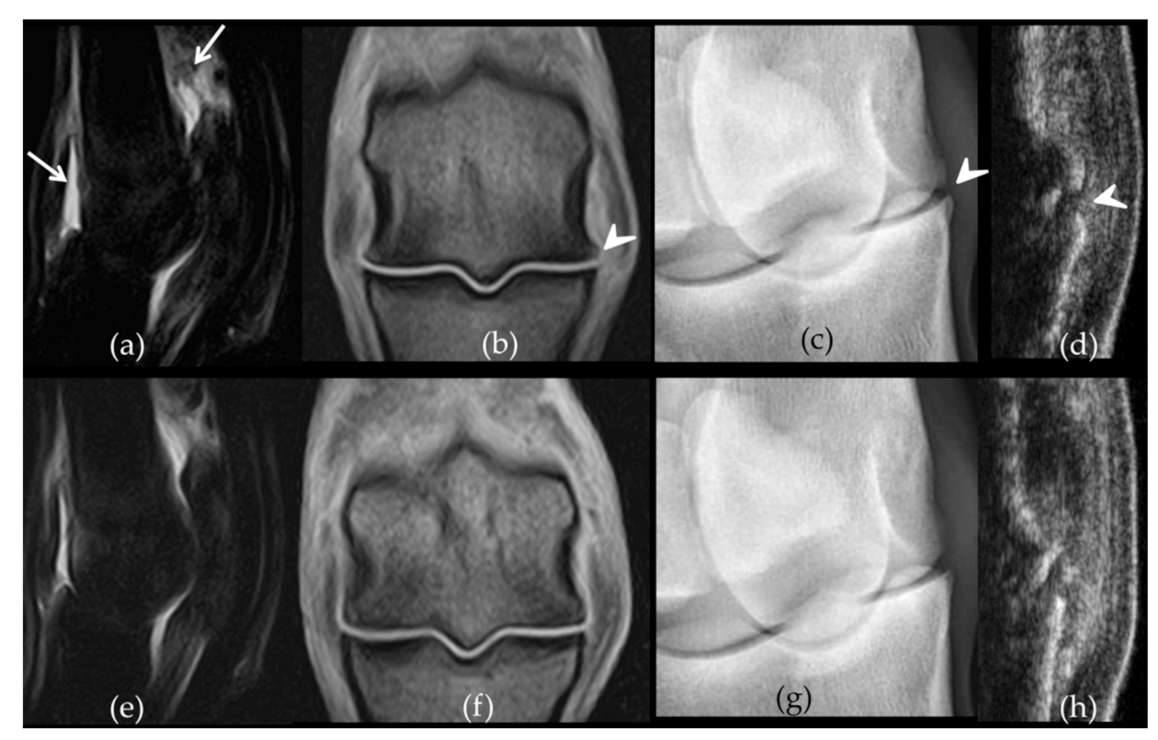

2.2. Follow-Up with Imaging Techniques

- Bertoni, L.; Jacquet-Guibon, S.; Branly, T.; Legendre, F.; Desancé, M.; Mespoulhes, C.; Melin, M.; Hartmann, D.-J.; Schmutz, A.; Denoix, J.-M.; et al. An Experimentally Induced Osteoarthritis Model in Horses Performed on Both Metacarpophalangeal and Metatarsophalangeal Joints: Technical, Clinical, Imaging, Biochemical, Macroscopic and Microscopic Characterization. PLoS ONE 2020, 15, e0235251. [Google Scholar] [CrossRef]